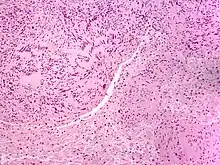

| Solitary circumscribed neuroma | |

A neuroma (/njʊəˈroʊmə/; plural: neuromata or neuromas) is a growth or tumor of nerve tissue.[1] Neuromas tend to be benign (i.e. not cancerous); many nerve tumors, including those that are commonly malignant, are nowadays referred to by other terms.

Neuromas can arise from different types of nervous tissue, including the nerve fibers and their myelin sheath, as in the case of genuine neoplasms (growths) like ganglioneuromas and neurinomas.